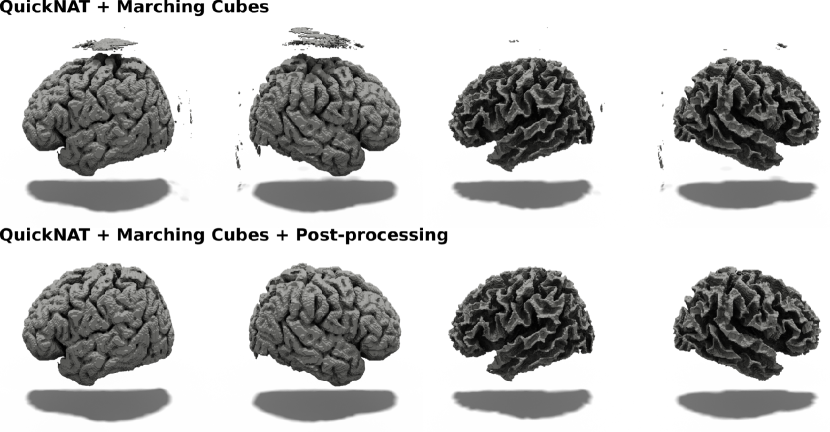

QuickNAT Baseline

The QuickNAT baseline consists of a voxel-wise segmentation model, iso-surface extraction method, and a mesh post-processing routine. More specifically, we first predict a segmentation of the input MRI into 28 anatomical regions using the QuickNAT [64] state-of-the-art segmentation model for brain segmentation. Second, we build the four cortical volumes by assembling anatomical structures contained in the four surfaces. Third, we run a marching cubes [42] algorithm to retrieve triangle meshes from the obtained binary segmentations. Since the resulting meshes present a lot of unwanted connected components (due to spurious mistakes in the segmentation), we only isolate the largest connected component using the trimesh.graph.connected_component_labels function. Figure 10 presents some meshes generated with this QuickNAT baseline. Our methodology was to get the best geometrical measure stemming from a segmentation-based approach. We verify that the suppression of small connected components improves all the metrics presented in our paper. Note, however, that those meshes cannot be used for the cortical surface reconstruction problem since they comprise hole and handle (not 0-genus). It is also important to notice that numerous errors are imputable to the limited resolution of this approach.